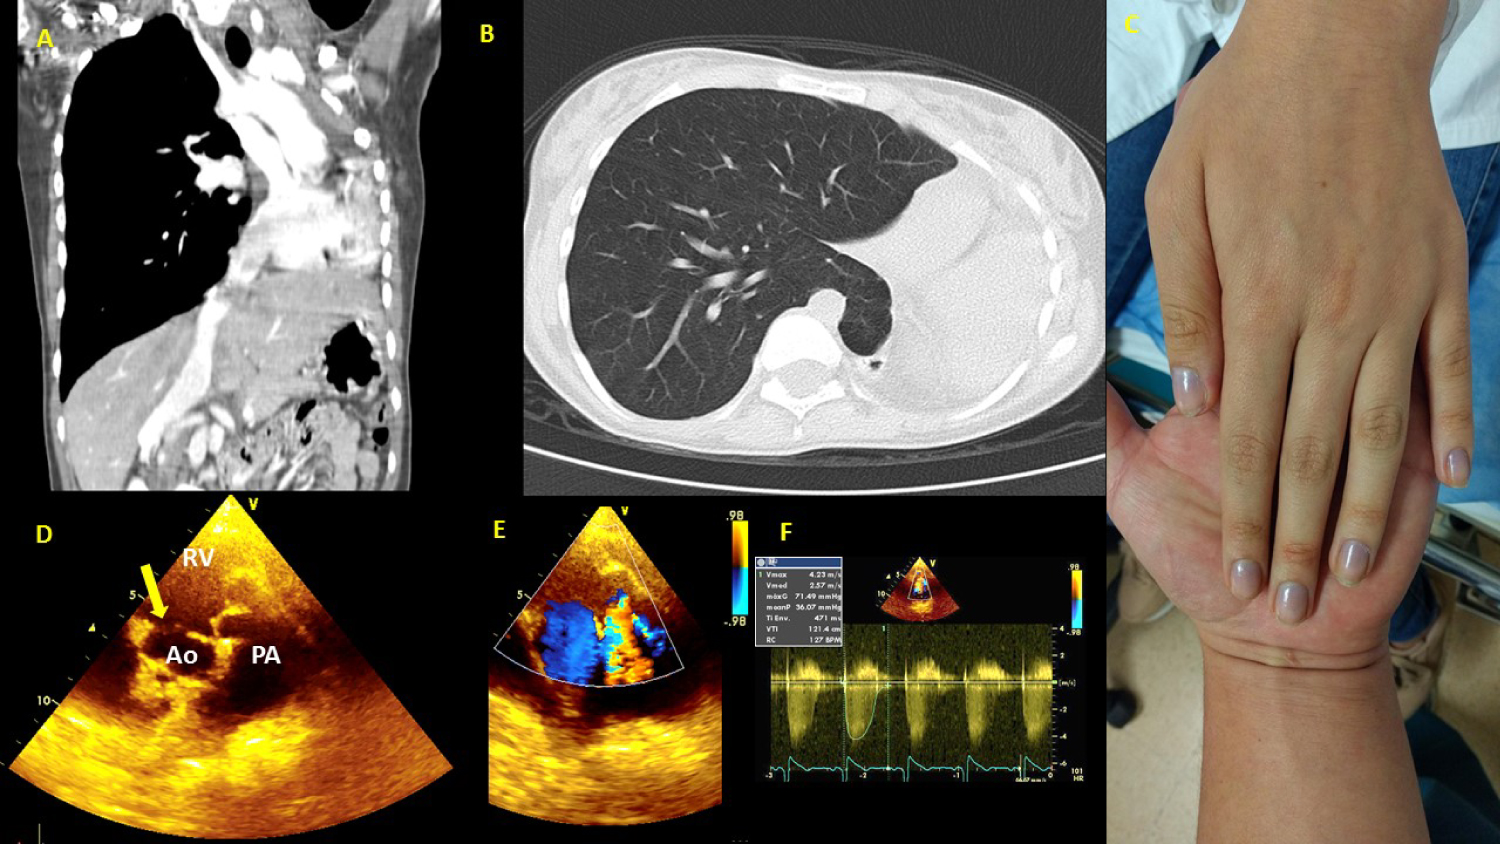

In patients with CHDs and baseline hypoxemia, the outcome is still unknown; however, it is assumed that, based on what has been explained, it could be very deleterious (Figure 3).

Figure 3: 16-year-old female with severe unrepaired CHD, multiple risk factors at the same time. (A) CT (Computed Tomography) thorax: Left lung agenesis, and important scoliosis; (B) CT thorax: Right lung hyperinflation compensatory, and herniation to left hemithorax; (C) Left hand showing marked central hypoxemia due to unrepaired severe CHD, saturation 75% on room air; (D) Echocardiography study: Short axis view shows double-outlet RV. Yellow arrow shows relationship between the VSD and the blood vessels; (E) The same view in D, doppler color shows pulmonary valve stenosis; (F) Doppler in pulmonary valve with 71 mmHg peak gradient. View Figure 3